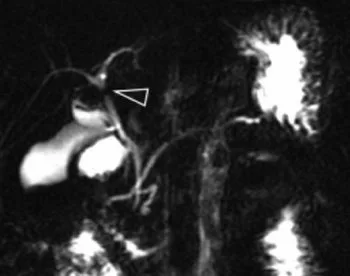

Figure 14. Les acquisitions 3D de bili-IRM apportent généralement un gain en résolution spatiale et en rapport signal sur bruit appréciable pour la recherche des signes de CSP. Mais lorsque la synchronisation respiratoire n’a pas été efficace, l’acquisition 3D sera de mauvaise qualité (A) et sera utilement complétée par des coupes 2D (B)